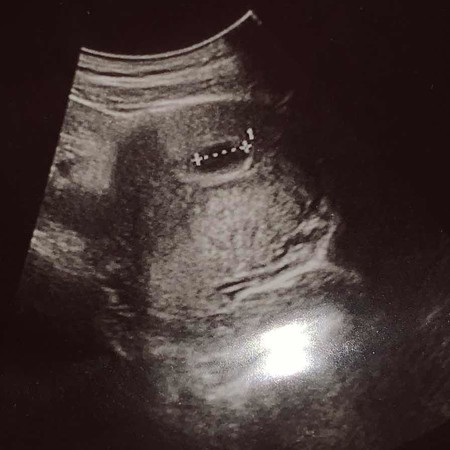

Scan 6w3d

Hi mommies! Nak tanya, ni scan sy masa 6w3d. Nampak kantung je tp tak nampak janin lagi. Saya check awal ke? Mommies ada yg mcm saya?

Ya mommies..masih terlalu awal tu..biasanya 9 minggu ke atas baru nampak janin..biasanya doktor akan suruh datang kembali ke klinik lepas 2 minggu kalau scan kali pertama tak nampak janin..😊